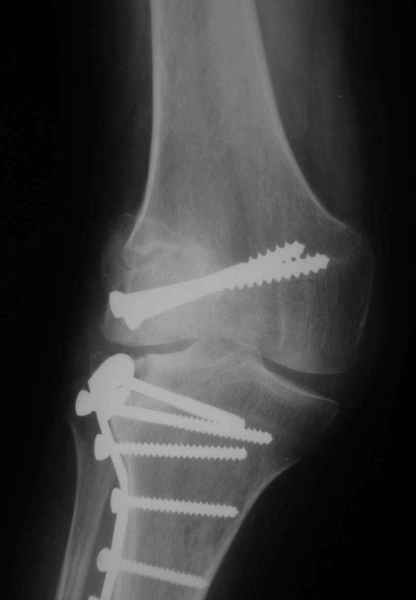

Как вариант решения прогрессирующей вальгусной деформации коленного сустава я бы предложил косую остеотомию дистального отдела бедра с фиксацией пластиной и компрессирующим винтом.

Взгляните на снимки , может быть это вам поможет.

Около 5 лет применяю этот тип дистальной остеотомии бедра для коррекции механической оси Н/К ( более 20 случаев) - достаточно эффективная операция.

Уважаемый Евгений ! Спасибо за ответ, но мне представляется, что в нашем случае основной проблемой является не столько прогрессирующий вальгус конечности, сколько несросшийся перелом мыщелка бедра и дефект мыщелка большеберцой кости - вероятно первичная репозиция выполнялась без пластики.

На своем горьком опыте убедился, что синтезировать мыщелковые импрессионные внутрисуставные переломы б\б кости без костной пластики - дело неблагодарное, рецидивируе деформация, мыщелок всегда *проваливается*. Чистые split type переломы можно ограничиваться и одной только межфрагментарной компрессией.

Может стоит сначала добиться сращения наружного мыщелка бедра( костная пластика) и коррекции оси?

Мне представляется, что прогрессирующий вальгус и обусловлен несросшимся переломом мыщелка бедра (томограммы -зона межфрагментарного склерозирования), а циклические нагрузки на сустав во время ходьбы усугубляют ситуацию. Как вы думаете, в этой ситуации насколько вероятен риск развития аваскулярного некроза мыщелка бедра?